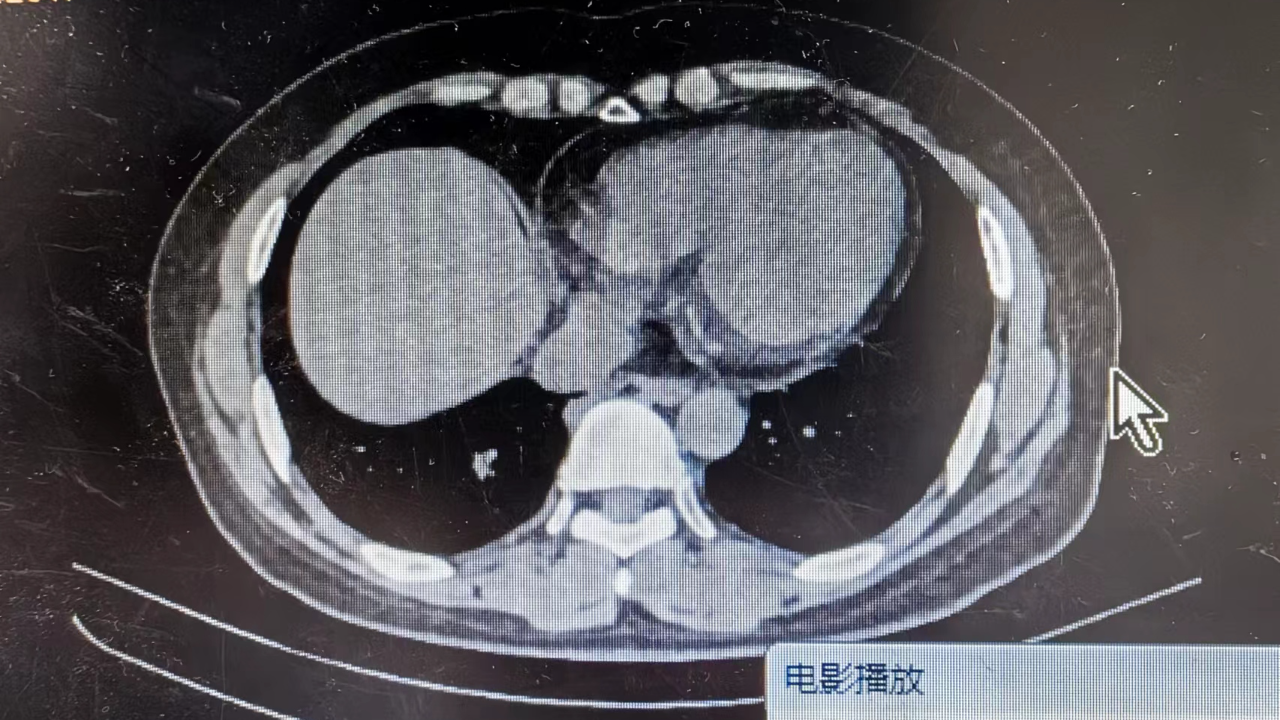

女, 50 岁,主因发现肺占位20余天于2024-06-11 17:05入院。

1.现病史:患者中年 女,患者于入院前20余天体检发现右肺占位,轻度胸闷、憋气,无发热,无咳嗽、咳痰,无胸痛,无咯血,无恶心、呕吐,无腹痛、腹泻,无抽搐及意识障碍,

上级医院会诊嘱咐详细询问病史,这个考虑什么疾病?